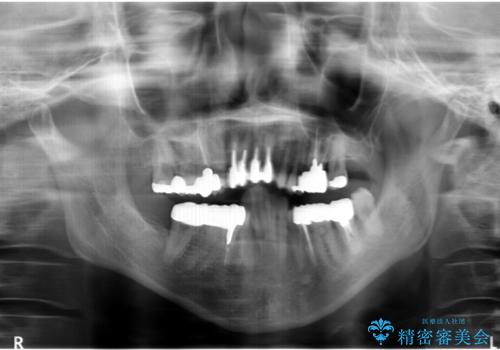

- 上顎前歯の黒ずみの改善、下顎前歯の十度なガタつき、矯正治療とセラミック治療を含む全体的な治療を希望され来院されました。

銀歯を高強度の仮歯に替えたのち、下顎前歯のみの部分矯正→全体的なマウスピース矯正治療(インビザライン)→最終的なセラミック治療と治療を進めます。

矯正治療と目立つ銀歯のやりかえを行ったことでかみあわせだけでなく、審美性・清掃性も改善し口腔内の環境を劇的に改善することができました。